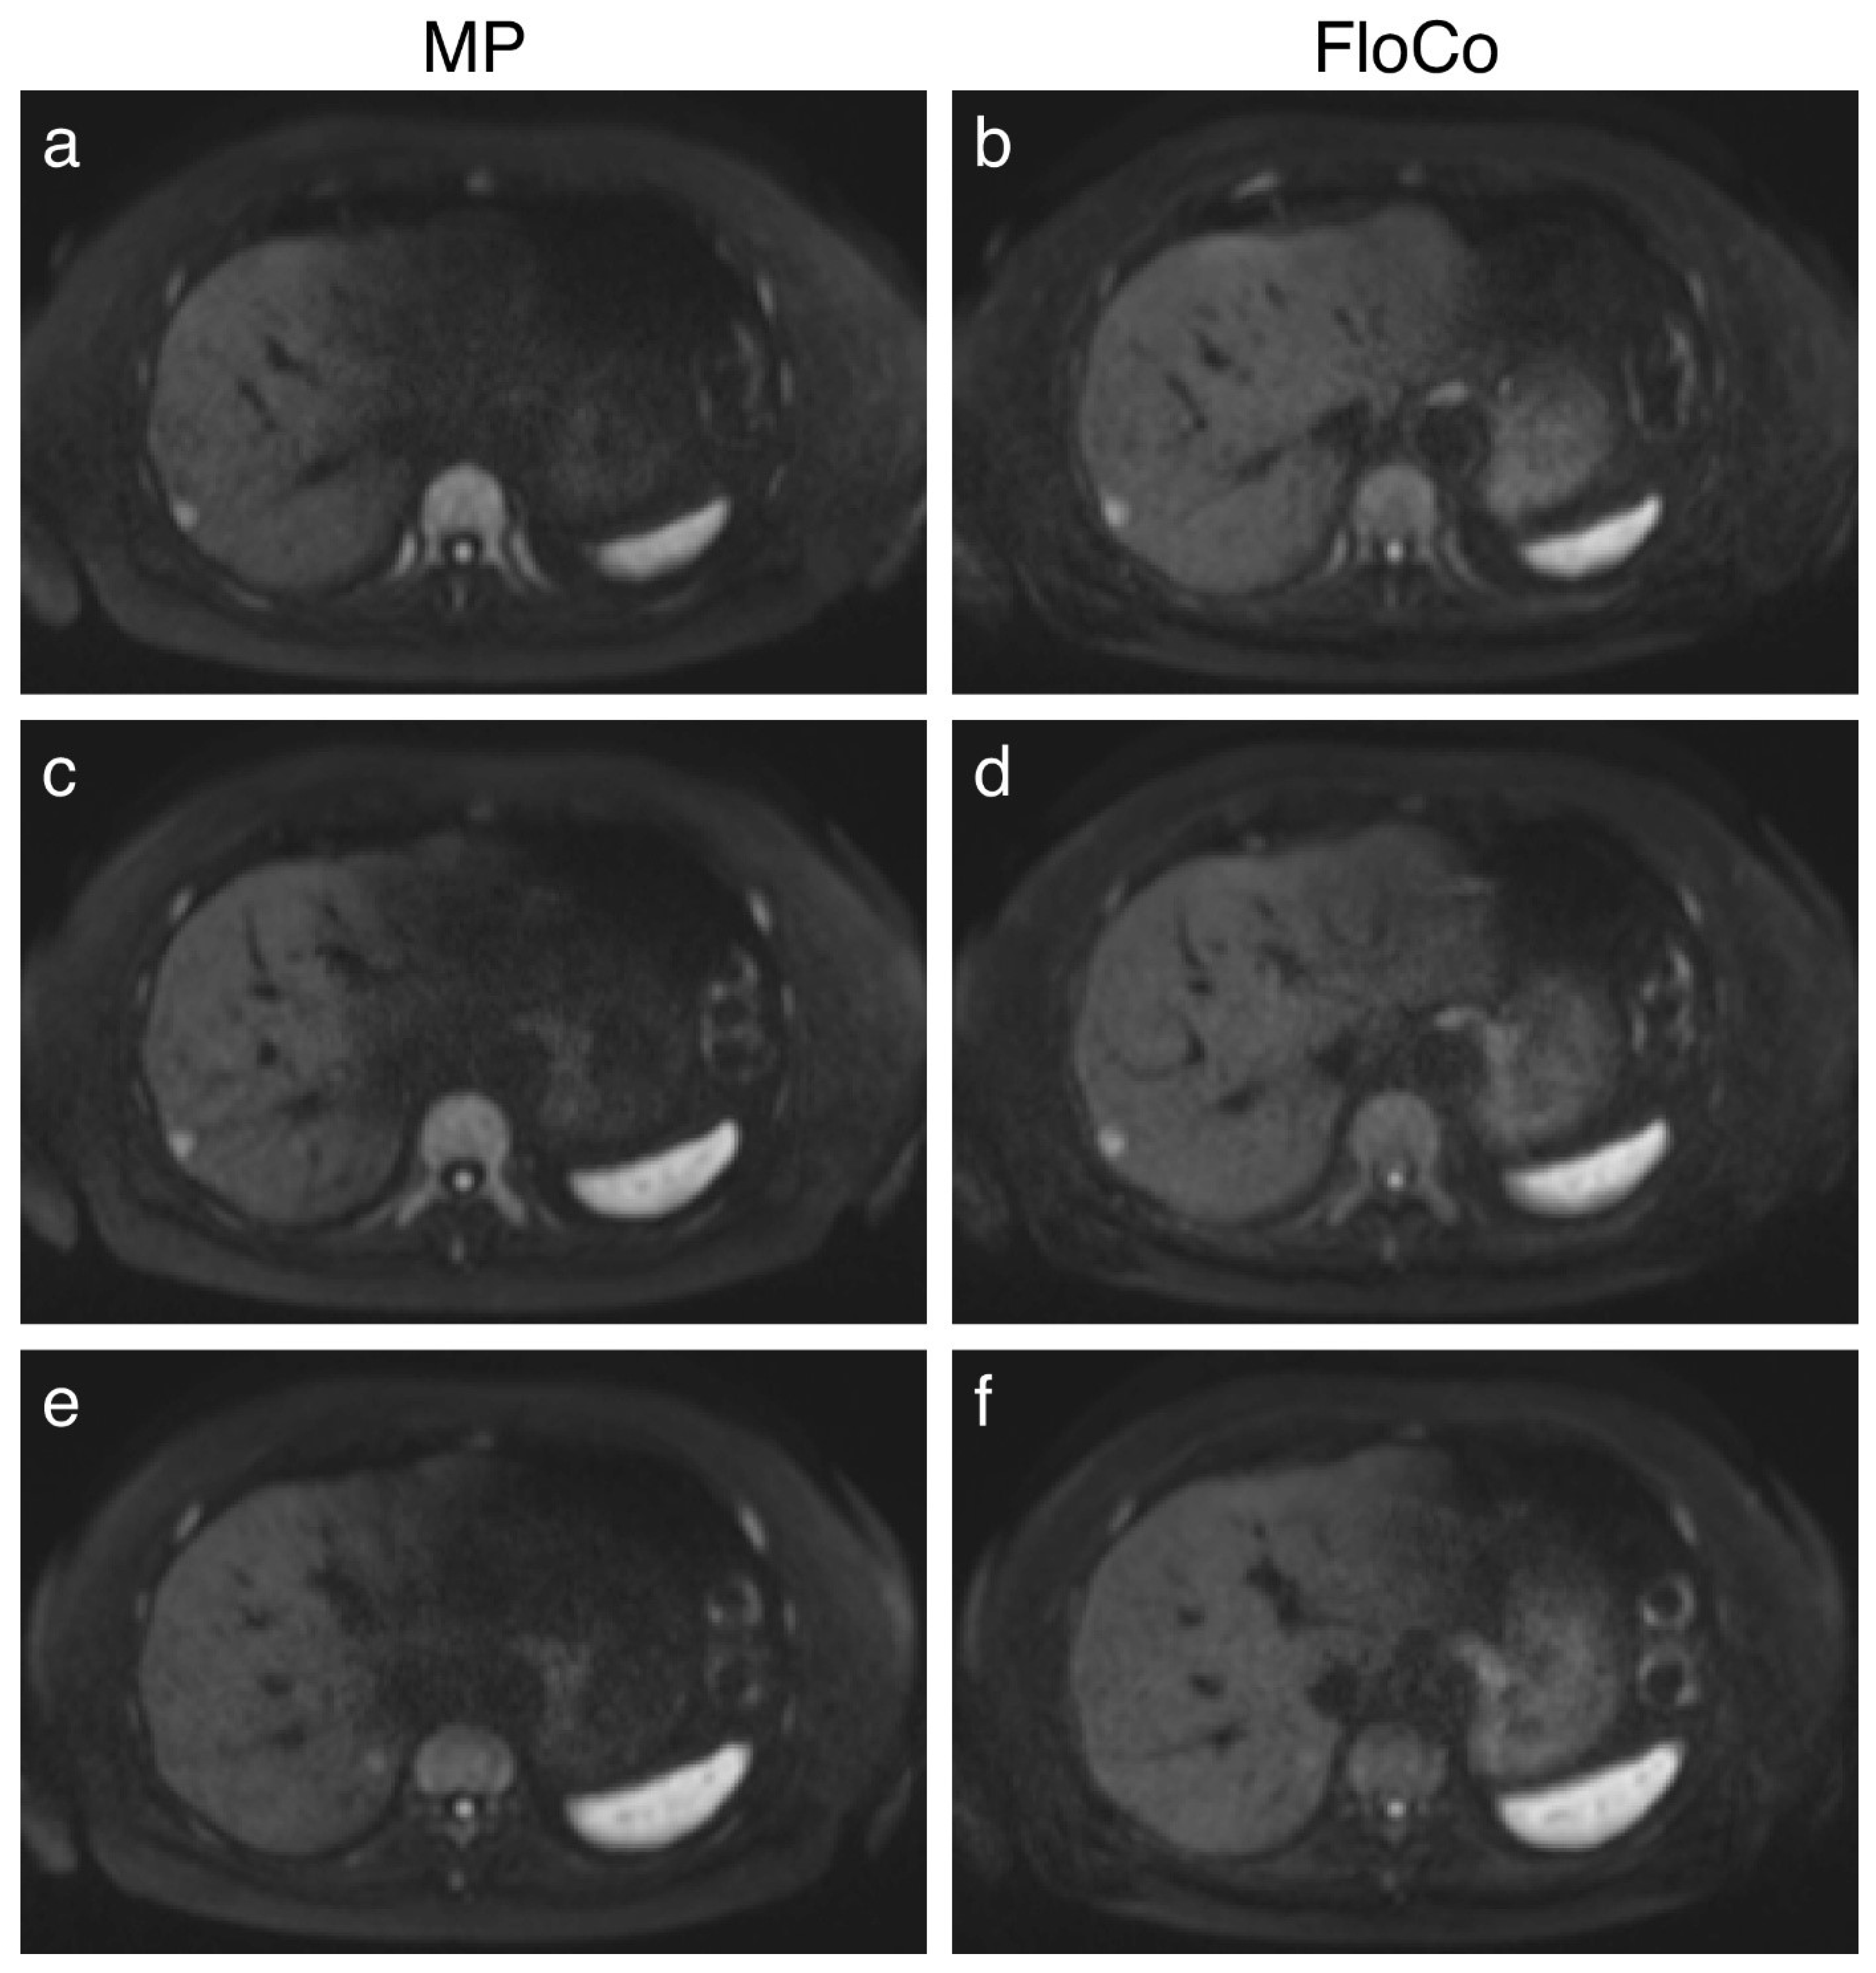

3.2. Representative Images